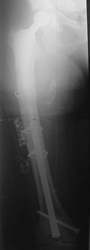

Ein Femurnagel wurde so zugerichtet, dass mit ihm die Prothesenspitze in einer Länge von 8 cm aufgefädelt wurde. Der Nagel wurde durch das Knie hindurch eingebracht. Distal wurde der Nagel verriegelt. Belastungsstabilität lag vor.